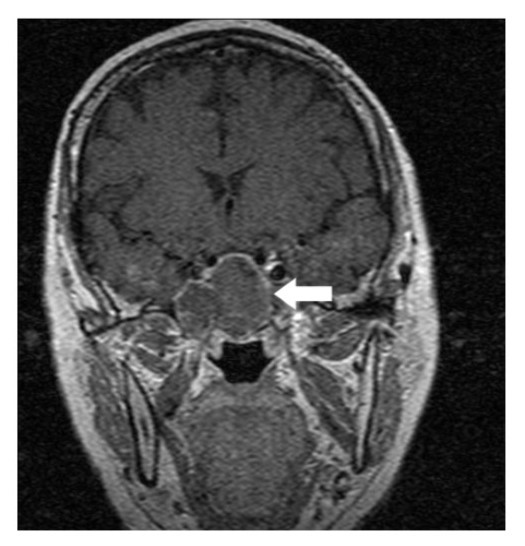

A 64-year-old lady presented to the outpatient department with complaints of headache and right eye blurring of vision for one month. Neurological examination revealed that bitemporal hemianopsia and impairment of visual acuity. Findings from fundus examination were within normal limits. Rest of the brain appeared unremarkable. Endocrine evaluation was normal. Results of renal function tests, liver function tests and haemogram test were within normal limits. A clinical diagnosis of non-secretory pituitary adenoma was made. Magnetic resonance imaging showed a well-circumscribed contrast-enhancing lesion in the sella (Figure 1, Figure 2). The patient underwent an endoscopic endonasal/transsfenoidal surgery in the supine position and total lesion resection was peformed. Intraoperatively, the lesion was found to be yellow colour, soft and avascular and it was removed totally until the sella turcica was visualized (Figure 3).In histopathologic examination septate hyphae were observed between inflammatory cells, Grocott staining is positive, but acid-fast stain for acid-fast bacilli (AFB) was negative. Histopathological findings suggest that infection of Actinomyces (Figure 4, Figure 5). We performed to patient consulted by patients to infectious diseases clinic. Patients underwent intravenous 6x2 gr ampicillin for four weeks.Then oral 4X500 mg amoxicillin treatment is planned a for at least 6 months. Patient did not have any deficits in the next six months.

Figure 2.White arrow shows on coronal section of MRI that a well-circumscribed contrast-enhancing lesion in the sella

Preoperative diagnosis of pituitary abcess is difficult because the presenting symptoms in these patients are similar to that in patients with pituitary adenomas 4. The most common symptoms are headache, vision disturbances and endocrinological abnormalities 5. Magnetic resonance imaging is the best imaging modality for sellar abscess and the features include a hypo- or iso-intense sellar mass on T1-weighted sequences and a hypointense mass on T2-weighted sequences pituitary abscesses may be divided into primary and secondary types. Primary pituitary abscesses occur within a previously healthy gland, while secondary abscesses arise within an existing lesion, such as an adenoma, craniopharyngioma, or Rathke's cleft cyst. Secondary abscesses share radiologic characteristics with the lesions from which they arise. The typical primary pituitary abscess gives the same or slightly lower signal than brain on T1-weighted images, and could be mistaken for a solid mass or presumed to represent a pituitary adenoma. Contrast-enhanced images are useful, demonstrating absence of central enhancement, suggesting a fluid or necrotic center 6.Actinomyces brain abscess is usually diagnosed based on the contrast enhancement on the periphery as in this case.Also MRI spectroscopy findings are the described in actinomyces infection 7, 8.